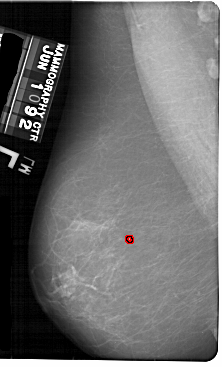

A_1864_1.LEFT_MLO

LEFT_MLO LINES 5491 PIXELS_PER_LINE 3316 BITS_PER_PIXEL 12 RESOLUTION 43.5 OVERLAY

FILE: A_1864_1.LEFT_MLO.OVERLAY

TOTAL_ABNORMALITIES 1

ABNORMALITY 1

LESION_TYPE CALCIFICATION TYPE PLEOMORPHIC DISTRIBUTION CLUSTERED

ASSESSMENT 4

SUBTLETY 2

PATHOLOGY BENIGN

TOTAL_OUTLINES 1

BOUNDARY